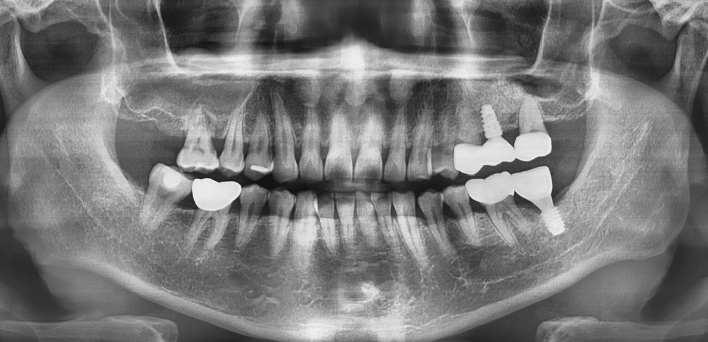

임플란트 케이스

임플란트 Before & After

The seoul dental clinic

※ 더서울치과의원은 의료법을 준수하며 위 케이스는 실제 환자의 동의를 얻은 사례로 치료 전, 후가 동일한 환경에서 촬영되었습니다.

환자 케이스에 따라 부작용이 발생할 수 있습니다. 이 부분은 의료진의 충분한 상담과 체크를 통해 예방하고 줄일 수 있습니다.

[임플란트 부작용] 수술 후 관리가 소홀할 경우 출혈, 주위염 등의 부작용이 발생할 수 있어 구강 위생을 철저히 유지하고, 정기적인 검진을 통해 상태를 점검하는 것이 중요합니다.